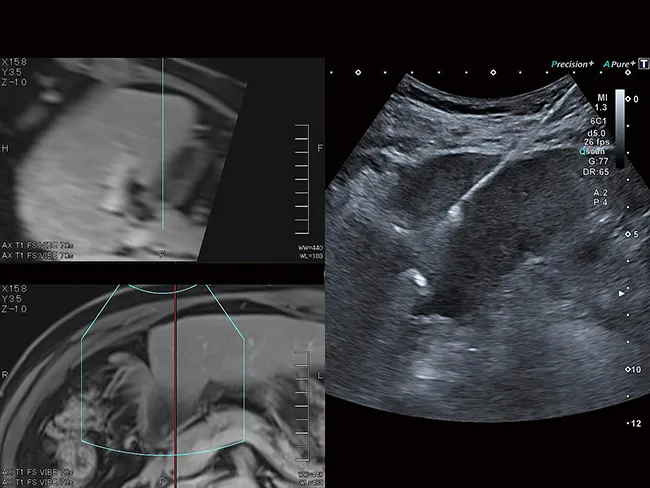

Smart Fusion объединяет ультразвук в реальном времени с ранее полученными данными КТ, МРТ или УЗИ, позволяя вам легко идентифицировать и сравнивать поражения и уверенно ориентироваться в сложной анатомии.